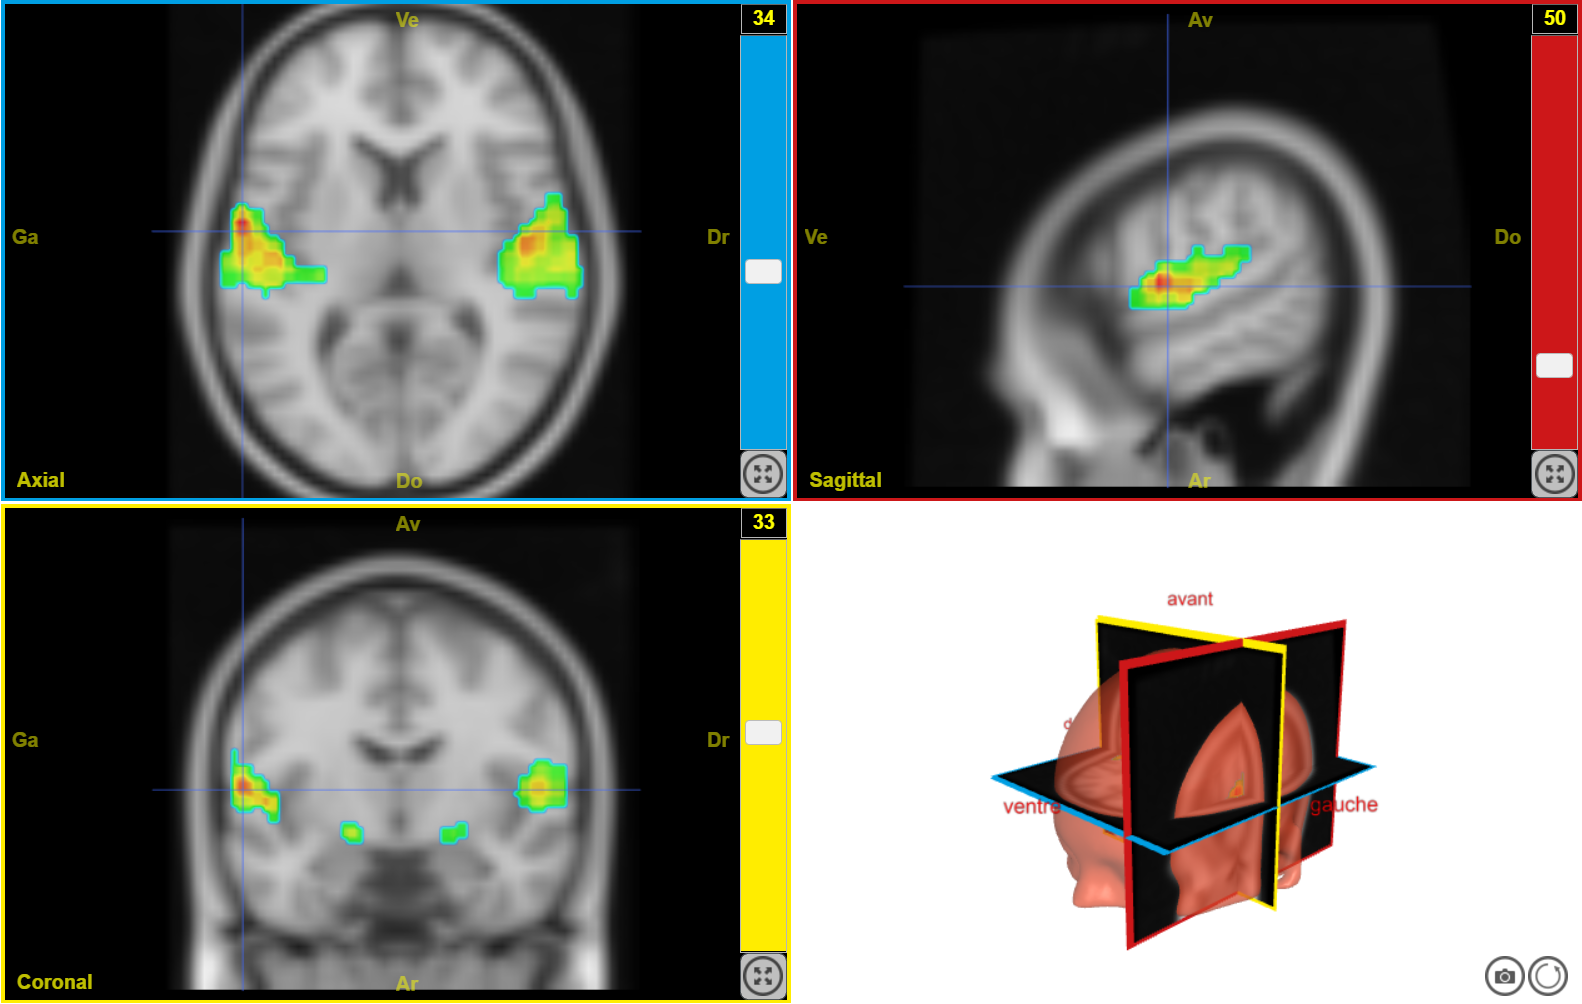

IRMf musique joyeuse 1